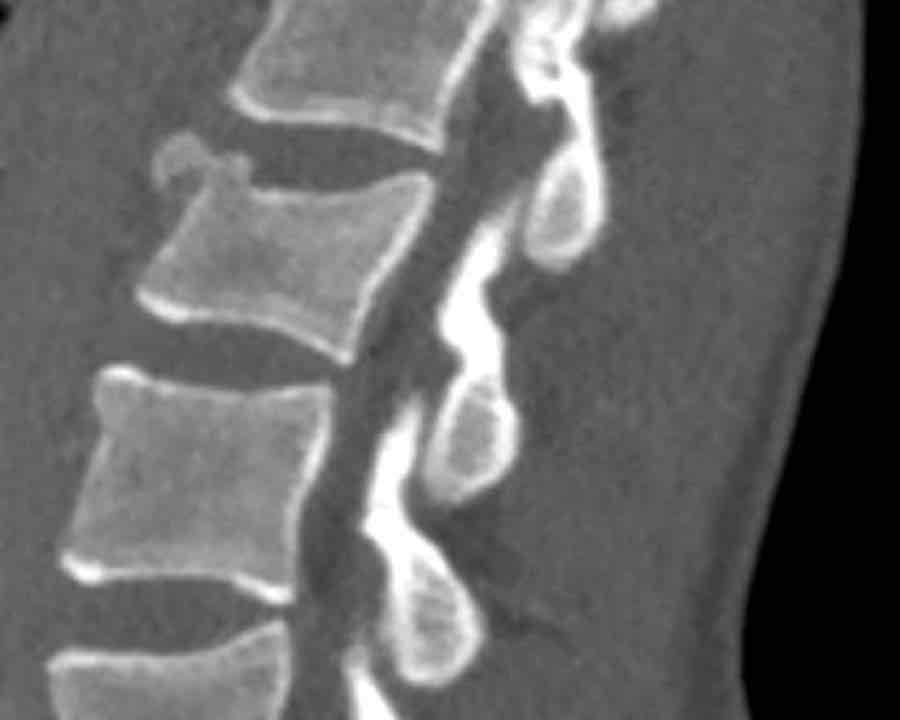

Findings

- Clear widening of the interspinous distance (yellow arrow)

- Black arrowhead: small avulsion fracture to the flexion distraction

- MRI better depicts the ligamentous injury, which was suspected on CT

Conclusion

Injury type B2

- Subtle widening of the interspinous distance (white circle)

- Small avulsion fracture spinous process (yellow arrow)

- Compression fracture with involvement of one endplate and posterior wall (1+2 points)

Injury type B2 + A3